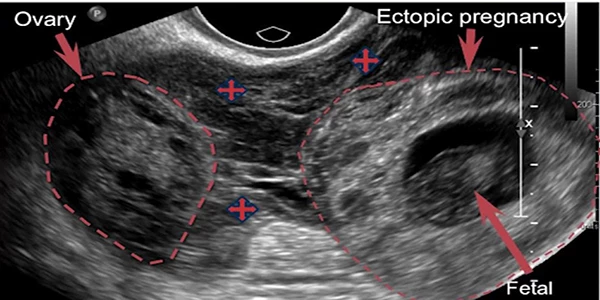

حاملگی خارج از رحم معمولا در لوله های فالوپ رخ می دهد، زمانی که تخمک ها از تخمدان می خواهند به رحم بروند. این نوع حاملگی خارج رحمی حاملگی لوله ای نامیده می شود. گاهی اوقات، حاملگی خارج از رحم در نواحی دیگر بدن مانند تخمدان، حفره شکمی یا قسمت پایین رحم (دهانه رحم) که به واژن متصل می شود، رخ می دهد.

حاملگی خارج رحم چگونه تشخیص داده می شود؟

اگر علائم پارگی لوله فالوپ را ندارید، ولی خونریزی غیر طبیعی واژن و درد شکم را دارید. پزشک متخصص زنان احتمال به بارداری خارج رحمی می دهد و برای اطمینان اقدامات زیر را توصیه می کند:

- معاینه لگن

- سونوگرافی

- آزمایش خون

اگر فرد سابقه حاملگی خارج رحم دارد و یا هر خانمی که باردار میشود، بهتر است بین هفته ۵ و ۶ یک سونو واژینال برای بررسی ساک حاملگی داخل رحمی صورت بگیرد.

ایا امکان اینکه یک جنین داخل رحم و دیگری خارج رحم باشد وجود دارد؟

بله